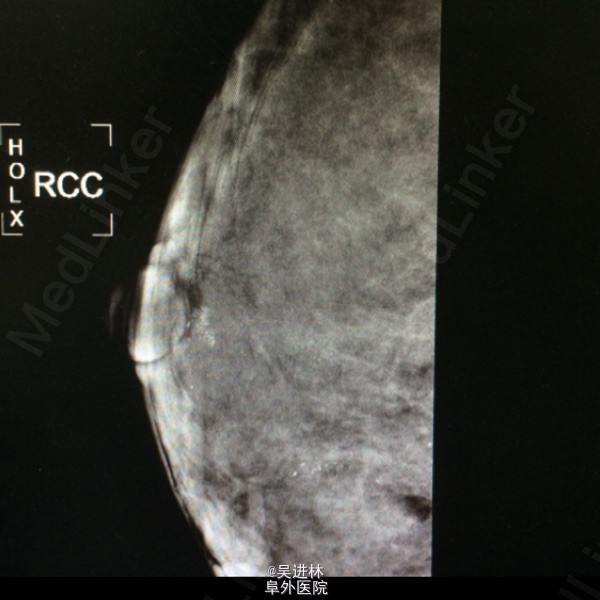

今天本来打算继续腹膜后脂肪肉瘤,但是悲闻姚贝娜因癌去世,遂借以下病例来谈谈乳腺癌钙化特点:患者中年女性,慢性起病,双侧乳房肿物4年余,以“双侧乳腺癌可疑”收入院。一般女性绝经候乳腺腺体开始萎缩,而此人腺体高度发达,脂肪组织几乎不可见,也是令人称奇(见钼靶)。查体双乳均可触及肿块,质硬,境界清,无压痛,表面欠光滑。腋下淋巴结未触及。钼靶显示双侧均可见簇状钙化。术前几乎被当作双侧乳腺癌来教学查房了一番,术后病理提示乳腺腺病。